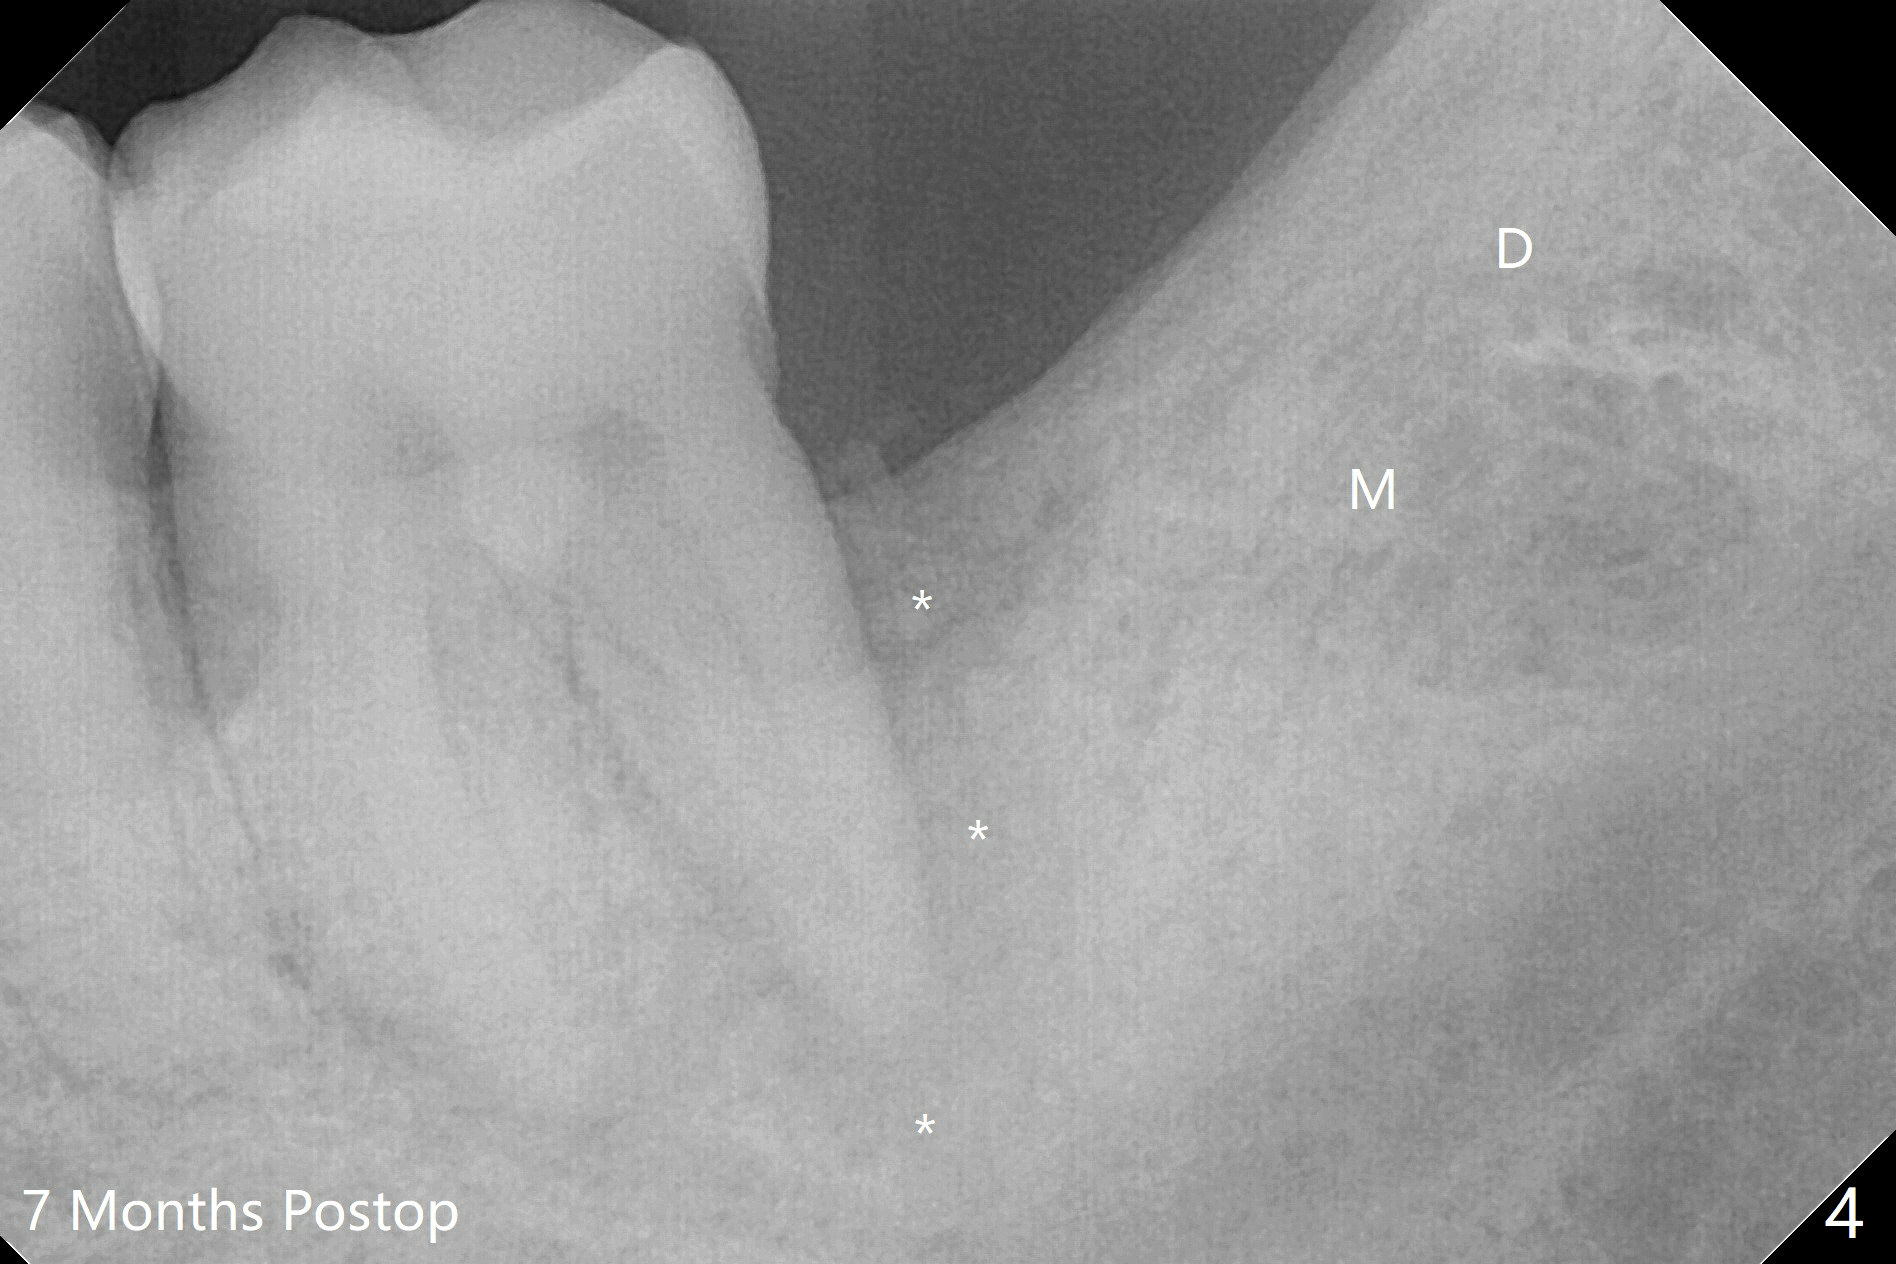

A 43-year-old man requests #17 extraction (Fig.1,2); the tooth #18 has large periapical radiolucency at the distal root. After SRP and extraction, Osteogen plug is placed in #17 sockets (Fig.3 P), while Vanilla Cancellous/Cortical Mix (allograft) 18 distal (*). The wound is closed with 4-0 plain gut suture. Similar to his son, he has crowding with #10 cross bite, #11 labioversion and a possible supernumerary tooth (11'). Seven months postop, not only does the periradicular radiolucency decrease around the distal root of the tooth #18 (Fig.4 *), but also the mesial and distal sockets of the 3rd molar heal (M, D). The patient is concerned about the sensitivity of the tooth #18, which is stable with the healthy gingiva. The sensitivity disappears 1 year postop, but there is a ~ 10 mm pocket distal of #18. Endo ice test shows necrosis. Endodontic referral is recommended. If endodontic treatment is not practical, periodontal referral is next step with laser modality.